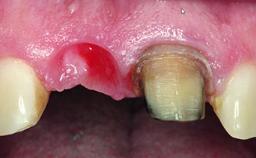

Replacement of a Failing Upper Left Central Incisor: Immediate Placement of an RC Bone Level Implant and Provisionalization

Loading Protocol Immediate

Provisional Implant-Supported Prosthesis Prosthodontic margin < 3 mm apical to mucosal margin Prosthodontic margin < 3 mm apical to mucosal margin